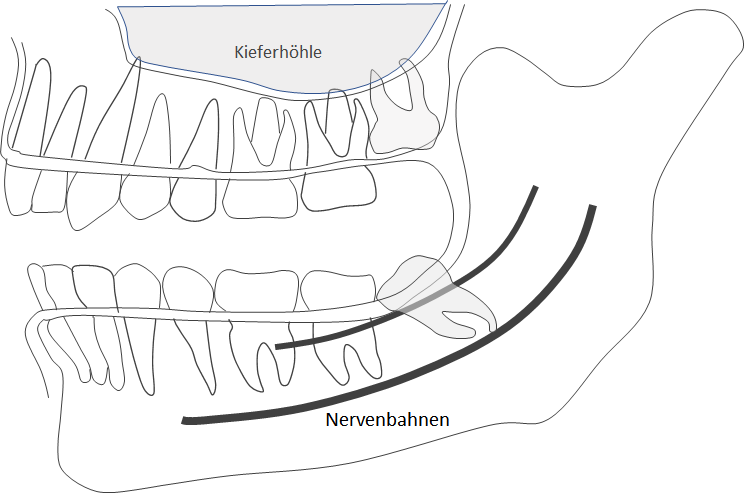

Weiter folgen aus dem freilegen des Zahnes gewisse Gefahren: Zum einen kann trotz sorgfältigem Vorgehen der Knochen beschädigt werden. Dies heilt in den meisten Fällen völlig aus. Jedoch gibt es Fälle, bei denen es zu einer dauerhaften Beschädigung kommt. Dies kann dazu führen, dass nachbehandelt werden muss. Solche Komplikationen sind allerdings selten (ca. 1 - 5 % der Fälle). Außerdem kann es zu Nachblutungen kommen, die allerdings nur kurze Zeit bestehen. Eine erhebliche Gefahr ist die Beschädigung von Nerven. Im Unterkiefer kommt vor allem eine Beschädigung des Nervus alveolaris inferior in Betracht. Dieser Nerv verläuft im basalen Bereich des Unterkiefers und die Zahnentfernung muss oft in seiner Nähe durchgeführt werden. Dies können Sie auf der Zeichnung gut erkennen. Durch eine sorgfältige Vorbereitung, insbesondere Röntgendiagnostik, kann eine solche Beschädigung fast immer vermieden werden. Kommt es doch zu einer Beschädigung, treten Schmerzen und Taubheitsgefühle im Versorgungsgebiet dieses Nervens ein, also vor allem an der Unterlippe und an den Zähnen der betreffenden Kieferhälfte. Auch der Zungennerv kann unter Umständen in Mitleidenschaft gezogen werden.

- Bei der Operation und durch eben genannte Folgen der Operation kann es zu Schädigungen und Beeinträchtigungen von Nerven kommen, die im schlimmsten Fall zum dauerhaften Ausfall führen können (Gefühlsstörung, Missempfindung, Taubheitsgefühl). Im Unterkiefer sind der Zungennerv (N.lingualis: für Geschmack und Gefühl im vorderen Zungenabschnitt zuständig) und der Unterkiefernerv (N.alveolaris inferior: für Gefühl der Unterkieferzähne und der Haut im Lippen- und Kinnbereich zuständig) in dichter Lage zum Operationsgebiet (siehe Abbildung auf der Vorderseite).

- Bei Therapiemaßnahmen im Oberkieferbereich kann es zur Eröffnung der Kieferhöhle kommen. Es wird die Kieferhöhle dann mit einer Naht und Schleimhaut aus der Wange verschlossen, so dass es nur in seltenen Fällen zur chronischen Kieferhöhlenerkrankung kommen kann.